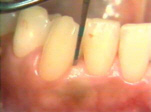

| Debajo de la

gingiva del incisivo hay cálculo subgingival observado cuando penetra

la sonda e inflamación del tejido. La gingiva también sangra fácilmente al sondear

la bolsa periodontal. |

En lingual de la mandíbula izquierda las señales de inflamación

gingival son muy prominentes. El tejido está hinchado, rojo, brillante y sangra muy fácilmente al sondear

los surcos gingivales. (Bolsas periodontales) |

En lingual de la mandíbula

derecha se encuentran los mismos signos que en la izquierda |